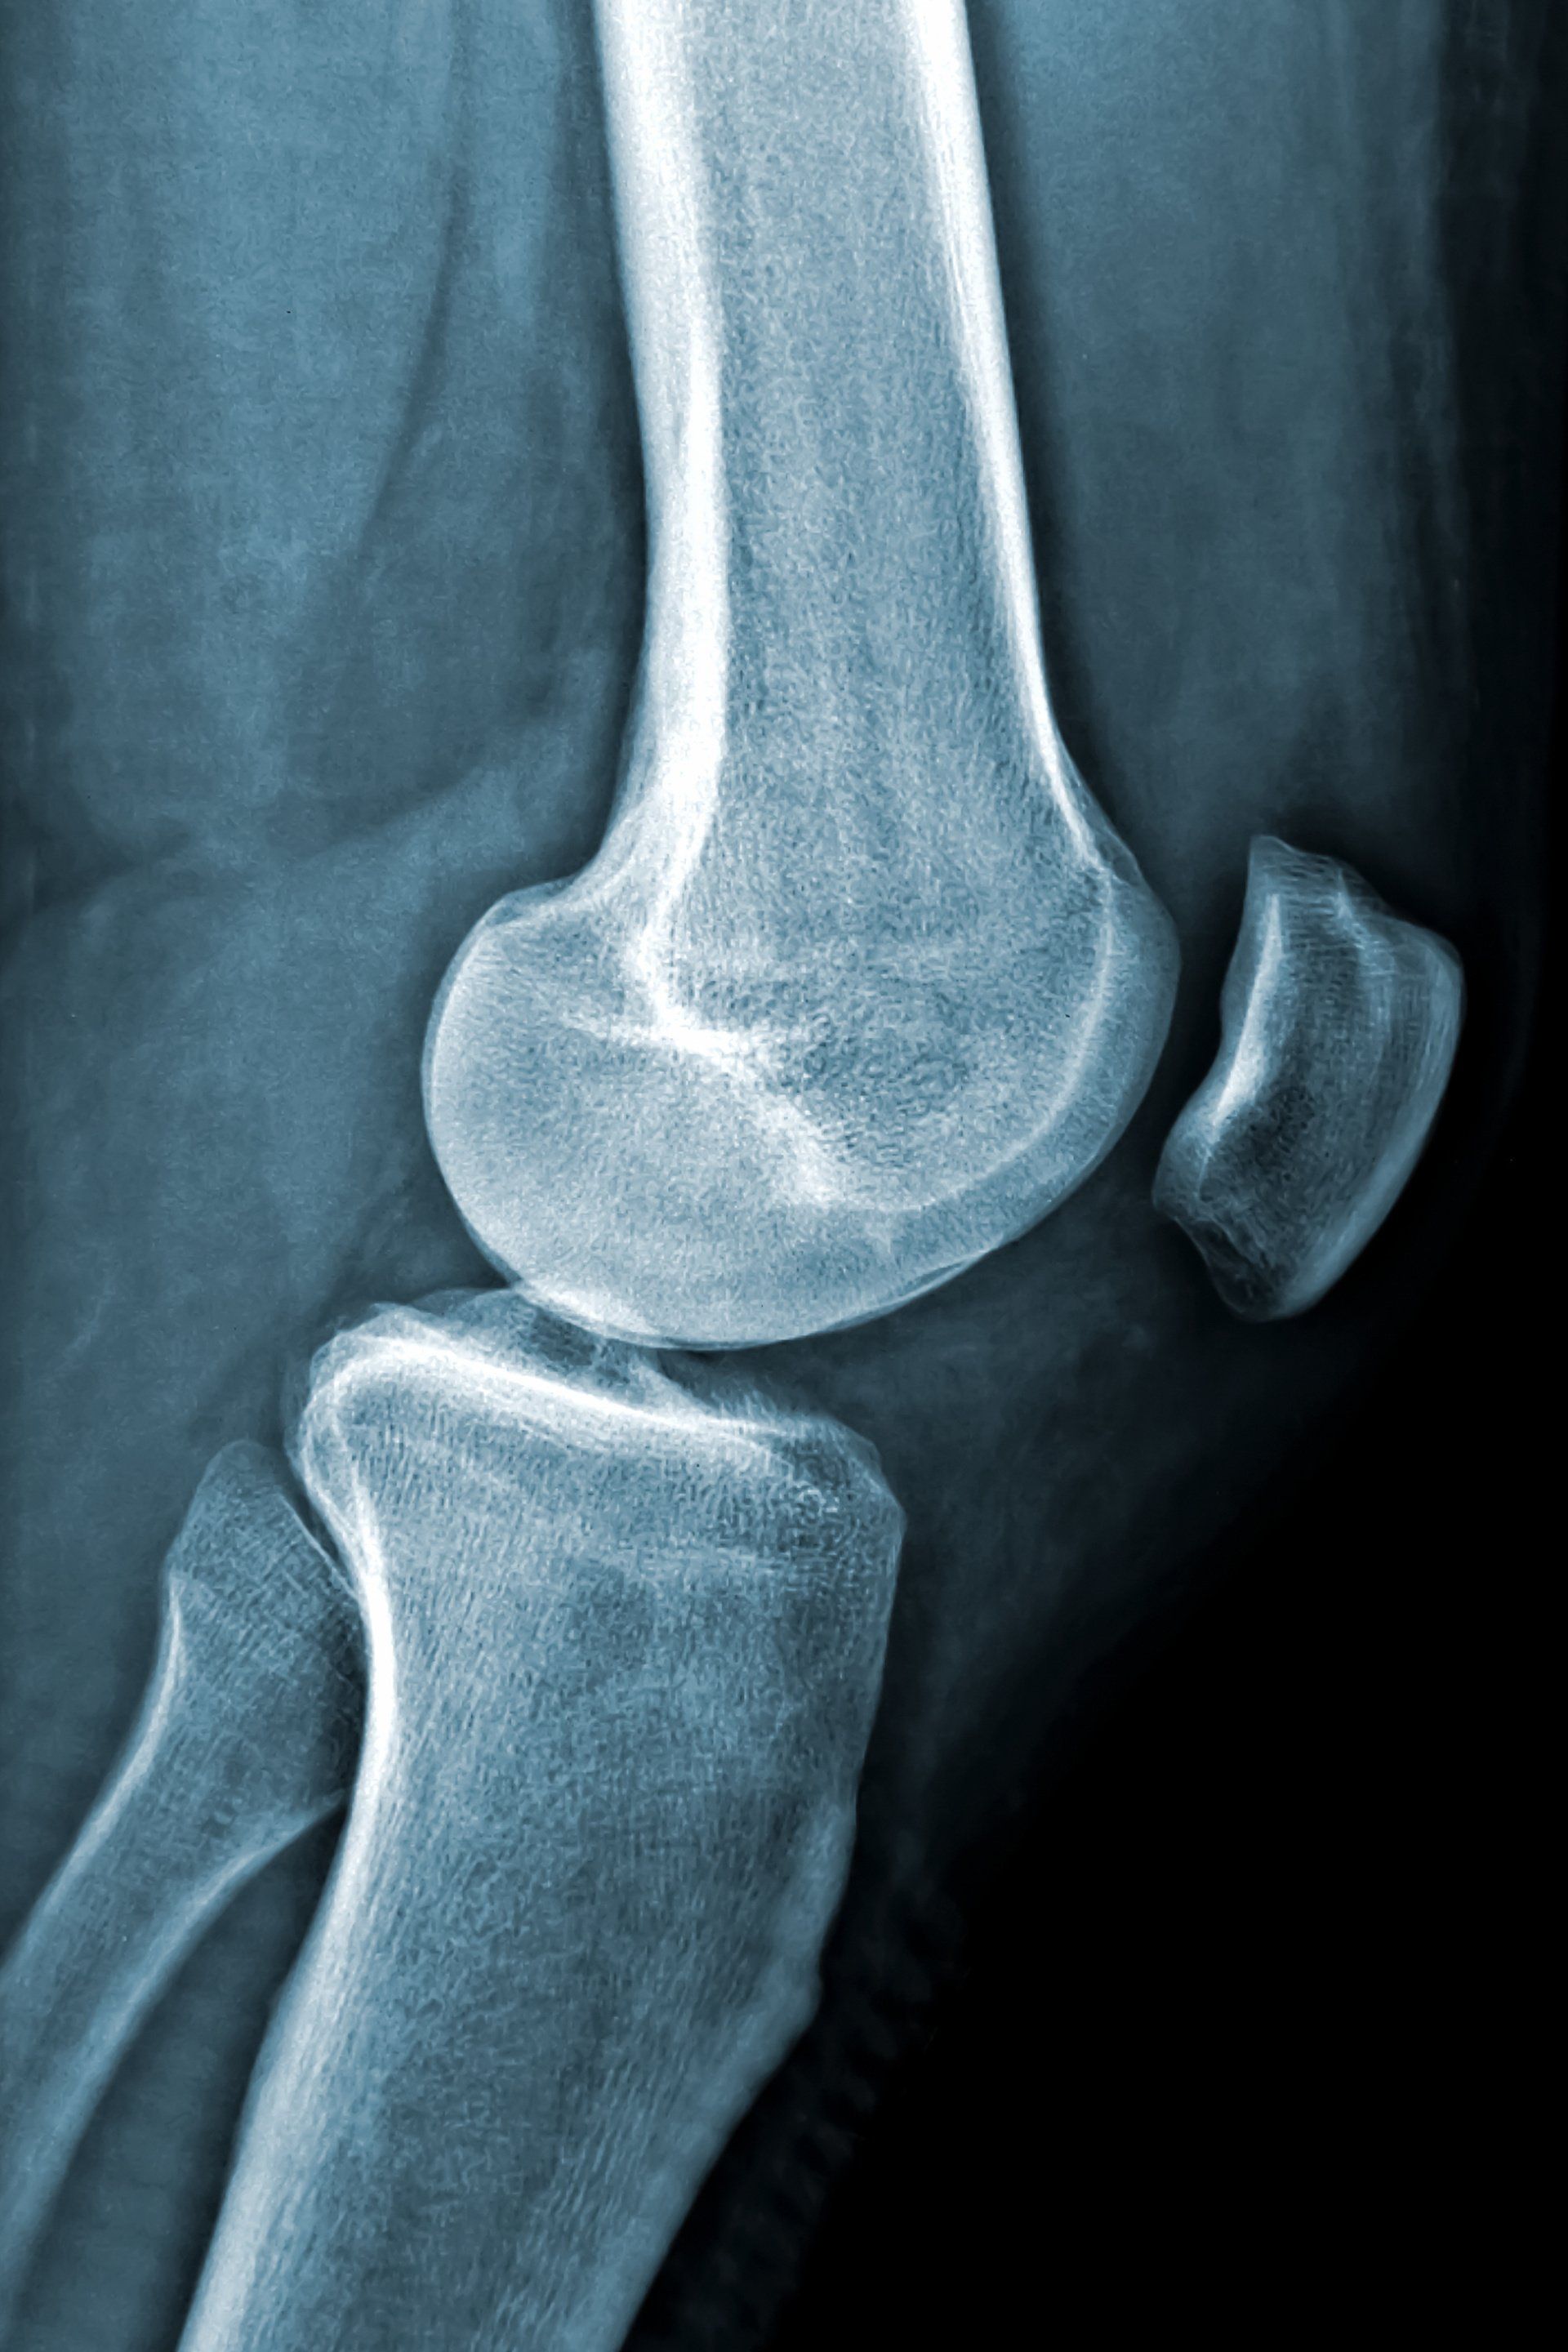

Πως διαιρείται κλινικά το γόνατο;

- Το γόνατο πρακτικά μπορεί να διαιρεθεί σε τρία μέρη:

- Το έσω μισό μεταξύ της κνήμης από κάτω και μηριαίου οστού από πάνω

- Το έξω μισό μεταξύ της κνήμης από κάτω και μηριαίου οστού από πάνω

- Επιγονατιδομηριαία άρθρωση μεταξύ της επιγονατίδας και του μηριαίου οστού